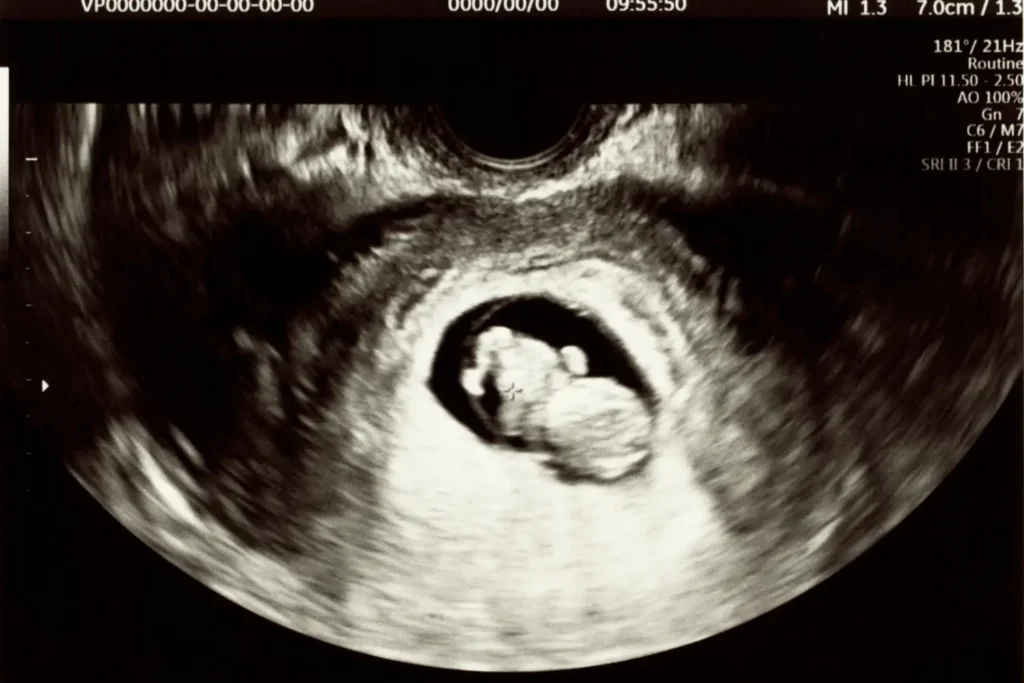

1. Early Pregnancy Scan (6 to 8 weeks)

Confirms intrauterine pregnancy, detects heartbeat, rules out ectopic pregnancy, and establishes gestational age. Particularly important for IVF pregnancies.